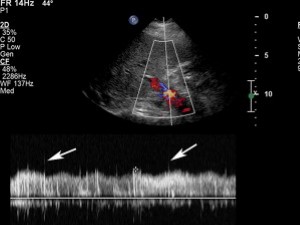

Hình 24. Hẹp đầu xa của TIPS ở bệnh nhân nữ 56 tuổi. (A) Ảnh siêu âm màu và Doppler cho thấy tốc độ tăng cao rõ rệt 376 cm/s ở đầu xa của TIPS. (B) Ở phần tĩnh mạch cửa (đầu gần) của TIPS. Tốc độ chỉ có 49 cm/s; sự chênh lệch tốc độ này chỉ ra sự chênh áp lớn trong shunt. (C) Dòng chảy tronhf tĩnh mạch cửa trái màu đỏ, chảy về gan, và rời xa TIPS khẳng định rối loạn shunt.

Những tiêu chuẩn đã mô tả trong y văn về chẩn đoán hẹp TIPS không được chấp nhận như nhau. Các nhóm tác giả khác nhau sử dụng các ngưỡng khác nhau với tốc độ trong stent khi đánh giá rối loạn chức năng. Tốc độ trong stent của TIPS thấp hơn 50 cm/s (khoảng giới bình thường từ 50 tới 90 cm/s) đã được coi là hẹp có ý nghĩa [27,28]. Tốc độ dòng chảy nên được đo ở cuối thì thở ra, bởi vì một nghiên cứu gần đây đã cho thấy rằng tốc độ trong TIPS giảm đến mức xấp xỉ 22 cm/s trong khi hít vào sâu [28].

Nếu có hẹp khu trú, người ta có thể thấy một vùng tăng tốc có chảy rối khu trú tại vị trí hẹp (xem Hình 24). Giới hạn trên của khoảng bình thường là từ 185 đến 220 cm/s, Middleton và cộng sự đã gợi ý ngưỡng 190 cm/s là tốc độ đỉnh tối đối với song Doppler xung đã chỉ góc [27].

Rối loạn chức năng của TIPS cũng dẫn tới giảm tốc độ trong thân tĩnh mạch cửa, với Middleton và cộng sự [27] đặt 30 cm/s là ngưỡng thấp của giới hạn bình thường [27]. Dòng chảy về gan ở nhánh tĩnh mạch cửa phải hoặc trái, rời xa TIPS khẳng định chẩn đoán [27].